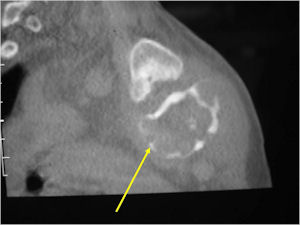

- The periosteum remains intact around the soft tissue component. Might need a CT scan to detect the subtle calcification (Egg Shell Rim of Calcification) associated with an intact periosteal reaction

- The lesion may be entirely radiolucent but usually shows some degree of mineralization. Mineralization may appear stippled like cartilage but do not see chondroid pathologically. Mineralization is sometimes better detected on a CT scan rather than an x-ray.

- More useful for detecting mineralization and evaluating extent of bone destruction than plain X-ray

- Soft tissue component usually surrounded by shell of reactive bone or periosteum (Egg Shell Rim of Calcification)